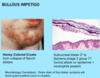

A: Describe Histology (3)

B: Dz

C: How would this appear Clinically

D: Tx

A: image

B: [SQC IN SITU] = BOWEN’S DZ

C: Plaque

D: Excision (will not regress on its own-but won’t metastasize once excised)